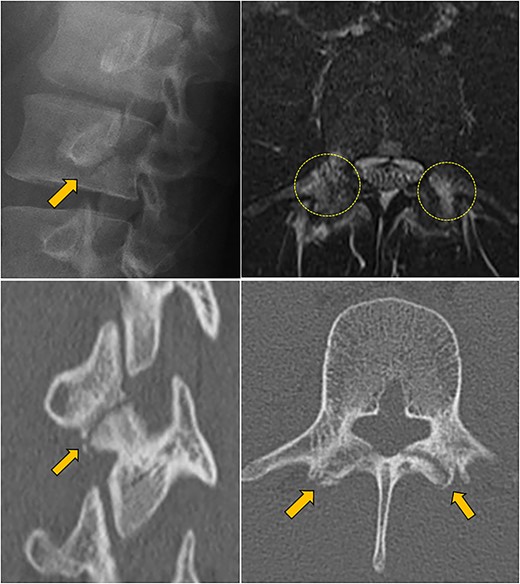

The patient was a 16-year-old boy, a javelin thrower. When throwing the javelin, he experienced severe low back pain and visited a nearby hospital. He had low back pain during extension of the lower spine. Plain radiographs showed pars fracture at L3. Despite stopping sports activity and wearing a hard brace for 6 months, he still had pain and was referred to our hospital. CT scans showed a complete fracture line, and T2-weighted MRI showed a high signal in the pedicles bilaterally (Fig. 1). We diagnosed progressive spondylolysis at L3. He strongly hoped for an early return to sports activity, and we scheduled surgical treatment.

Preoperative lumbar X-ray, MRI, and CT scan; upper left: oblique view X-ray showed a complete fracture line (arrow); upper right: horizontal T2-weighted MRI showed a high signal area in the pedicles bilaterally (circles); lower left, right: oblique and horizontal CT scan showed a complete fracture line in the pars (arrow).